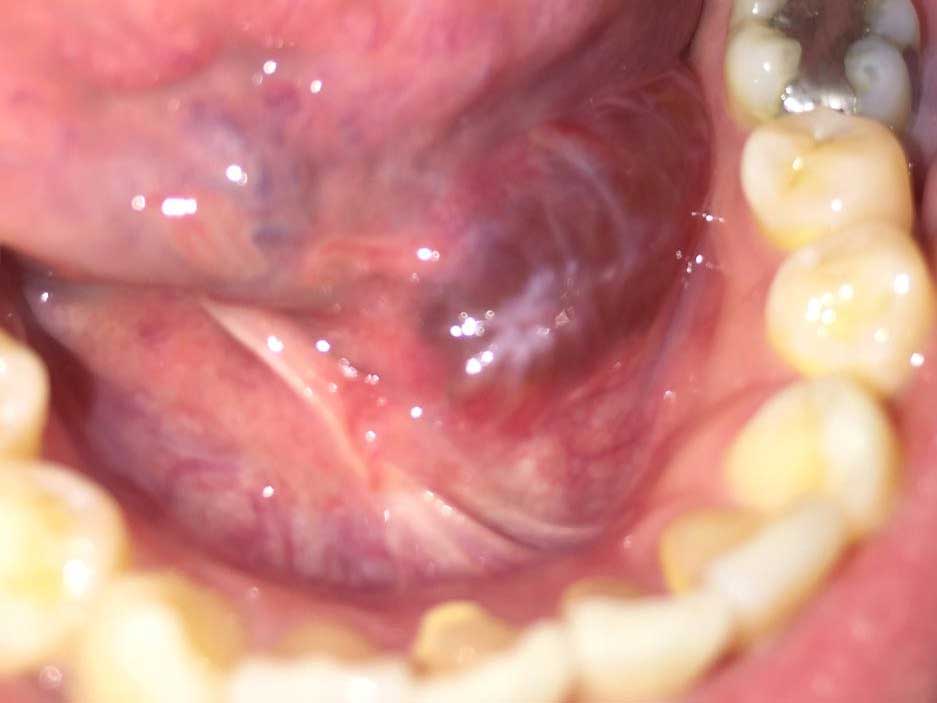

左舌下囊腫

約兩個月前, 我左舌下生了個泡, 大大下會破, 流出好似蛋白連些血絲的液體, 並不痛。

後來看了私家醫院的專科, 醫生指我有RANULA, 已在9月中做切除sublingual salivary gland手術, 手術後傷口埋口後, 由10月開始傷口再有腫起的情況, 而且愈來愈大, 至今並有3-4次大至破了,再流出之前出現的液體。問之前做手術的醫生,他表示並不是復發,是傷口埋得不貼,如我有需要可以幫我用有紋的線再縫,幫助傷口埋得貼地D。我感到很疑惑,想知自己的情況應該如何是好?

妳好!Ranula連同sublingual gland割除後,仍有機會復發。從相片來判斷是否復發,並不凖確,須作臨床檢查才可知道。